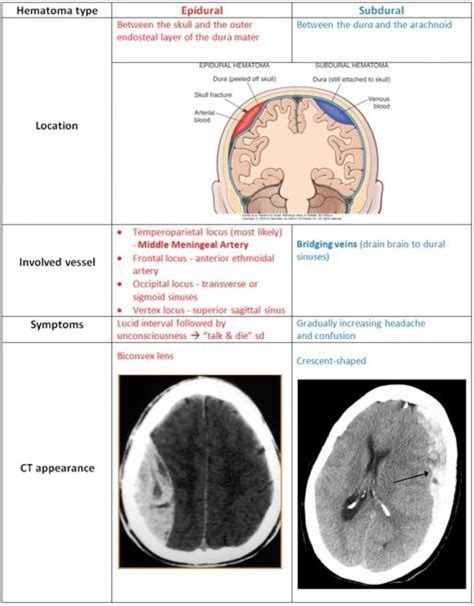

While both epidural and subdural hemorrhages involve bleeding in the brain, they have distinct characteristics that set them apart. Here is a comparison of the two conditions:

Characteristic Epidural Hemorrhage Subdural Hemorrhage

Location of Bleed Between the dura mater and the skull Between the dura mater and the arachnoid mater

Common Causes Trauma to the head, often associated with skull fractures Trauma to the head, brain atrophy, or other medical conditions

Symptom Onset Rapid, often within minutes to hours Gradual or sudden, depending on the type (acute or chronic)

Diagnostic Tools CT scan, MRI CT scan, MRI

Treatment Options Emergency surgery, medications, monitoring Observation, medications, surgery

Understanding these differences is essential for accurate diagnosis and effective treatment.